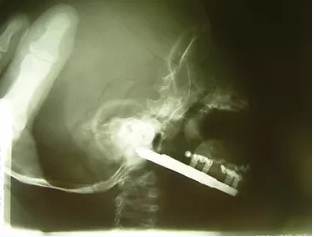

Синдром (секвенция, последовательность, аномалад) Пьера Робена - это врожденный порок развития, который характеризуется резким недоразвитием нижней челюсти, расщелиной твердого и мягкого неба, глоссоптозом. Вследствие резкого уменьшения просвета дыхательных путей, возникающего в ответ на уменьшение размера нижней челюсти и смещения тканей дна полости рта кзади, язык занимает приподнятое положение с тенденцией к опрокидыванию. Анатомическая деформация верхних дыхательных путей приводит к возникновению у детей синдрома обструктивного апноэ во сне, синдрома внезапной смерти, поражению сердца и его проводящей системы, возникновению системной гипертензии малого круга.

Лечение новорожденных детей, родившихся с этим заболеванием зависитот клинических проявлений дыхательных нарушений и от результатов проведенного полисомнографического исследования. В случае имеющегося у ребенка СОАС легкой или средней степени тяжести лечение проводится с применением силиконовых вестибулярных пластинок. В случае если у ребенка имеется СОАС тяжелой степени тяжести, ребеку показана операция по удлиннению нижней челюсти

В последнее время, для лечения детей с синдромом Пьера Робена, в России и за рубежом активно внедряется в практику метод компрессионно-дистракционного остеосинтеза. Данный метод имеет явные преимущества по сравнению со всеми остальными. Они заключаются в том, что этот метод малотравматичен, физиологичен, имеет стойкий результат. (Дубин С. А. 2005, Рогинский В. В. Комелягин Д. Ю. 2006г., Топольницкий 0. З. 2005).